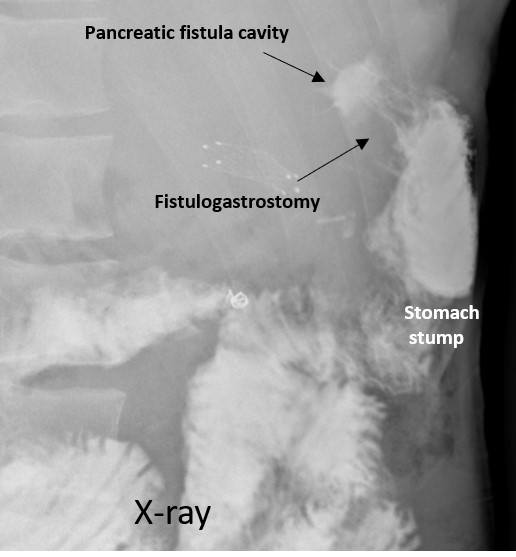

Эндоскпические исследования и фистулография привели нас к решению о возможности образования постоянного сообщения между культей желудка и подкожным расширением свищевого хода — полостью, в которую изливался панкреатический сок, перед тем как вытекать наружу. Риск такого вмешательства заключался в том, что ситуация могла значимо ухудшиться, если бы не панкреатический сок стал бы поступать в желудок через сформированный канал, а наоборот, желудочное содержимое присоединилось бы к панкреатическому соку, увеличив отделяемое по наружному свищу. После всесторонних измерений и взвешивания за и против, Елена Николаевна Солодинина установила специальный сетчатый стент (см. рентгеновский снимок) через стенку культи желудка в расширение свищевого хода c помощью системы Hot Axios. Это было непростым делом, т.к. полость была небольших размеров и требовала расширения в процессе вмешательства. В результате, спустя месяц после процедуры, можно было утверждать, что свищ закрылся, стент был удален, и на гастроскопии видно хорошо сформированное сообщение между полостью свищевого хода и желудком. Никита впервые за 15 лет почувствовал себя здоровым, стал активным, устроился на работу.